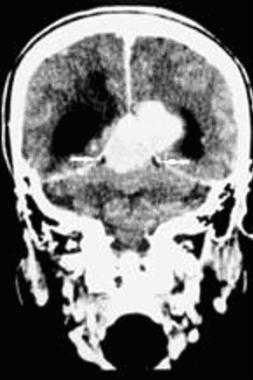

З адняя тенториальная менингиома на корональном КТ-изображении с контрастным усилением. К намету мозжечка прилежит объемное образование повышенной плотности с четкими краями. Визуализируются застой спинно-мозговой жидкости, легкий отек прилежащих тканей, гомогенный характер контрастирования, а также расширение желудочков.